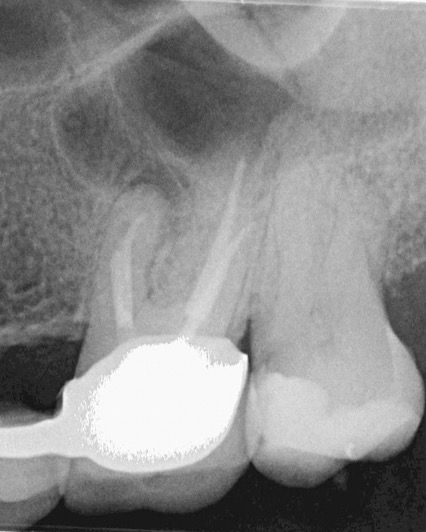

45 yaşında sağlıklı kadın hasta, 2023 Mayıs ayında protetik gereksinimden dolayı prepare edilen 26 numaralı dişinde işlem sonrası gelişen şiddetli ağrı şikayeti ile kliniğimize başvurdu İlgili dişe kök kanal tedavisi işlemi planlandı (Şekil 1).

(Şekil 1) 2023 Mayıs 26 No Pre-Op radyografi.